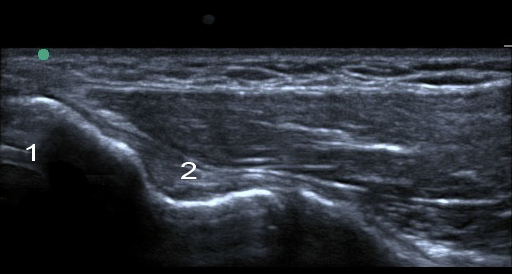

肘尺骨側副靱帯の画像

内側上顆

内側側副靱帯(UCL)